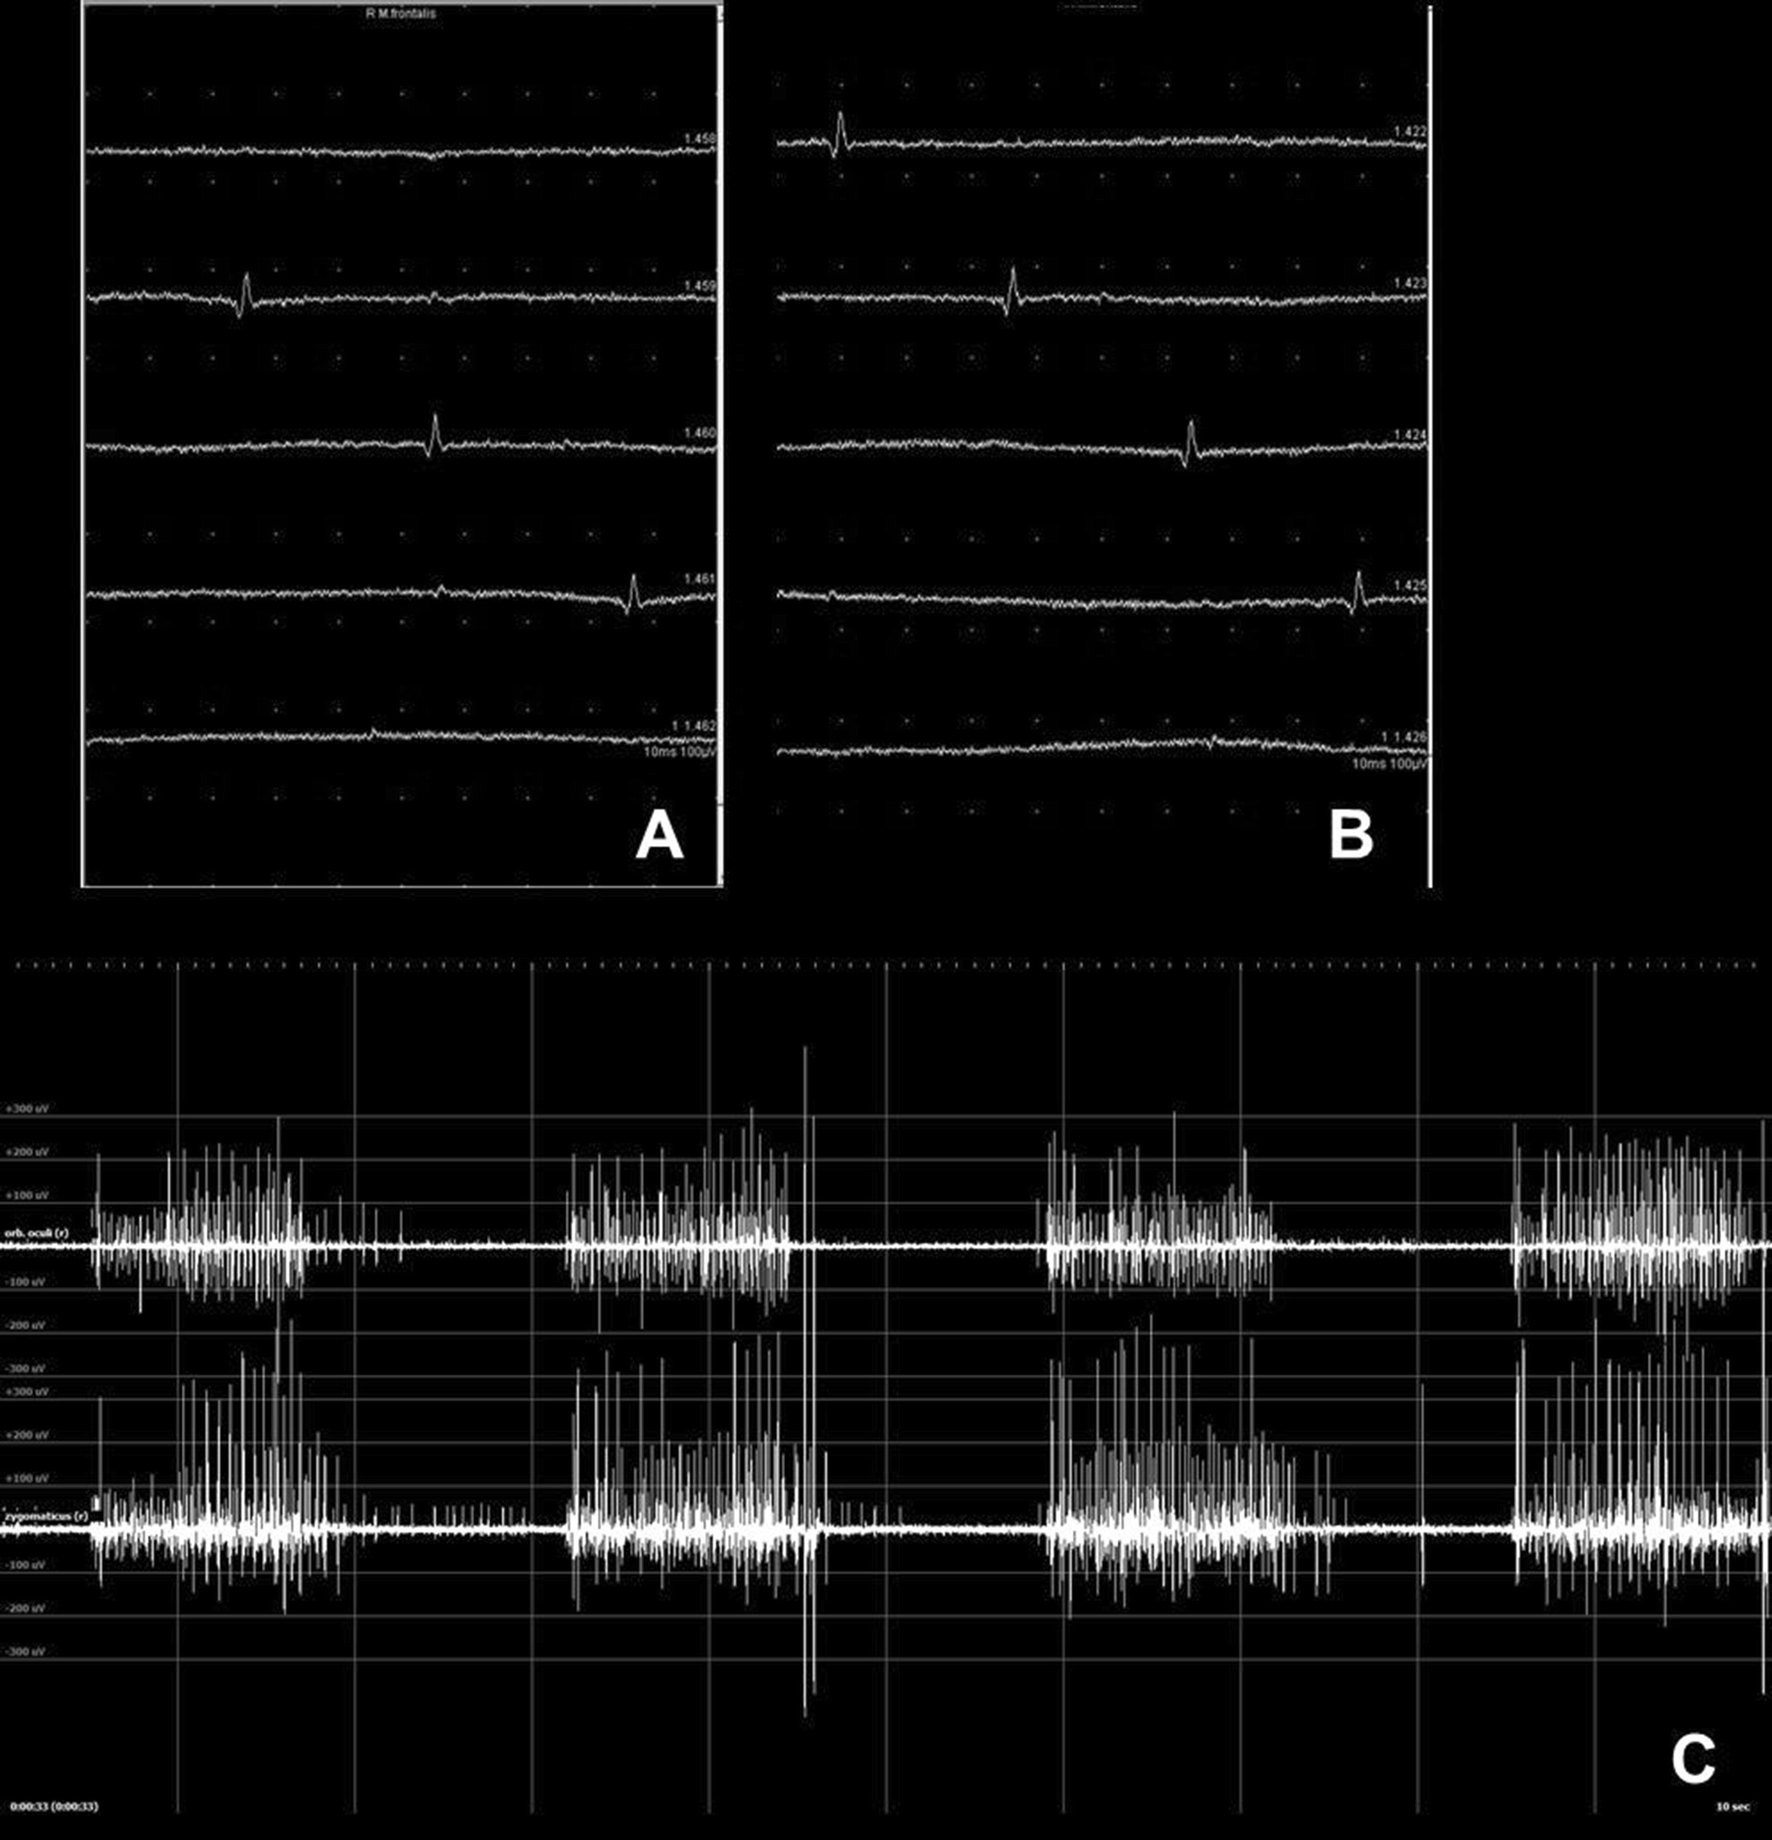

Fig. 3

Needle electromyography (nEMG) recordings at rest and during activity: a, b Two different examples of pathological spontaneous activity as a sign for nerve denervation in patients with facial nerve infiltration by a malignant parotid tumor and facial nerve lesion in temporal bone trauma, respectively, c 2-Channel-recording simultaneously of two muscles. Recording of the orbicularis oculi muscle (upper channel) and zygomaticus muscle (lower channel) showing synkinetic activity (setting shown in Fig. 5): While closing the eye not only the orbicularis oculi muscle is activated, but also simultaneously the zygomaticus muscle as a sign for aberrant reinnervation in a patient with post-paretic synkinesis

Activity during voluntary muscle movement

This part of the nEMG examination requires the assistance of the patient. The patient is instructed to follow a standard task, frowning for the frontalis muscle, closing the eye for the orbicularis oculi muscle, showing the teeth for the zygomatic muscle etc. The stronger the muscle contraction is, the result is a greater number of activated MU and a denser MU activation pattern (Fig. 4). Facial nerve lesion may lead to a reduced number of normal MUAPs and reduced recruitment during voluntary activity. The patient is instructed to vary the force of activation from minimum to maximum and back. The maximum activation pattern is evaluated. The number of impaired facial nerve axons is directly related to a decrease in the EMG interference pattern. The electrophysiological configuration of MUs is normally not changed in patients with neurapraxia. The duration of MUs and the number of their potential phases typically are increased in patients with axonotmesis or neurotmesis. If the facial nerve regenerates, spontaneously or after nerve repair, facial axons reinnervate the target muscles. A typical sign of reinnervation is polyphasic regeneration potentials. These MUs have greater amplitudes than normal and a prolonged duration during the regeneration process.